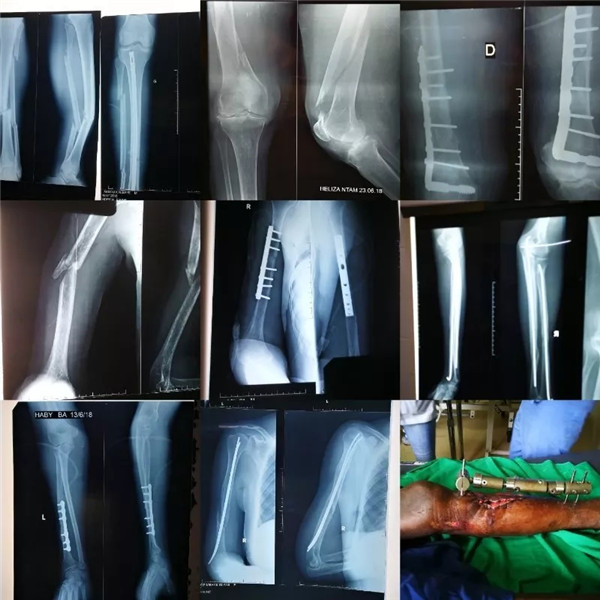

骨科病人在这家医院占有相当大比例,也许是医疗体制的问题,骨科患者基本是手术当日住院,术后基本3-4天出院,骨折手术的患者基本是陈旧性复杂困难大。骨科病人多,一个手术日基本5台左右,早上开始一直持续到结束经常是下午5点左右,中午也就是找个空隙填个肚子。

部分病人的影像照片